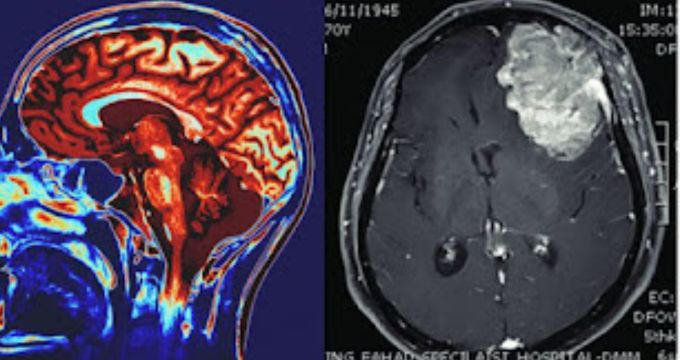

মহানগর ডেস্ক: বিজ্ঞান অলৌকিক ঘটনায় বিশ্বাস করে না। প্রমাণ ছাড়া এগোতে চান না বিজ্ঞানীরা। তবে মাস কয়েক আগে এমন একটি ঘটনা ঘটে,বুদ্ধিতে যার ব্যাখ্যা পাওয়া সম্ভব হয়নি। এক “সম্মোহিত” হওয়া মহিলা শুনতে পেয়েছিলেন (Miracle Voice Told She Has Tumour) কেউ তাঁকে বলছেন সিটি স্ক্যান  করানোর জন্য। কারণ তাঁর মাথার ভেতর টিউমার  রয়েছে। ভারী,গম্ভীর গলায় কেউ যেন কথাগুলো বলে চলেছে আর সেই কথাগুলো তিনি শুনে চলেছেন। এমন কথা শোনার পর তাঁর মাথায় সিটি স্ক্যান করা হয়।

দেখা যায় সত্যি সত্যি মহিলার মাথার ভেতর রয়েছে এক টিউমার। এক টুইটার ইউজার ওই মহিলার অস্বাভাবিক ঘটনা পোস্ট করার পর তা ভাইরাল হয়ে যায়। ওই টুইটার ইউজার লিখেছেন এক অদৃশ্য সম্মোহনকারী গলায় বার্তা পেয়ে তাঁর মাথার টিউমার অস্ত্রোপচার হয়।

এরপর তিনি রিপোর্টের লেখকের সঙ্গে দেখা করেন। এরপর ফাংশনাল হ্যালুসিনেটরি সাইকোসিসের মাধ্যমে রোগ নির্ণয় হওয়ার পর তাঁকে আবার ধ্যান করতে বলা হয়। কাউন্সেলিংও চলে। কিছু সময়ের জন্য সেই সম্মোহনও বন্ধ হয়ে যায়। তবে বিদেশে ছুটি কাটানোর সময় ফের তিনি সেই সম্মোহনকারী গলা শুনতে পান। তখন সেই গলার স্বর তাঁকে বলে তাঁর মাথার ভেতর টিউমার রয়েছে এবং মস্তিষ্কের কোষে প্রদাহ হচ্ছে।

তাঁকে স্ক্যান করার নির্দেশ দেয় সেই গলার স্বর। এরপর ওই মহিলা এবং চিকিৎসকের দল সেরা টিউমার চিকিৎসা কীভাবে যত তাড়াতাড়ি সম্ভব, তা করার ব্যাপারে আলোচনা করেন। ওই সিদ্ধান্তকে সমর্থনও জানায় সম্মোহনকারী গলা। অস্ত্রোপচারে টিউমার বের করার পর আবার তিনি সেই গম্ভীর গলা শুনতে পান তারা জানাচ্ছে টিউমার বাদ দেওয়ার জন্য তারা খুশি। তাঁকে সাহায্য করতে পেরে খুশি জানিয়ে থেমে গিয়েছিল গলার স্বর। তারপর বহুদিন কেটে গেলেও সেই গলার স্বর আর শোনা যায়নি।